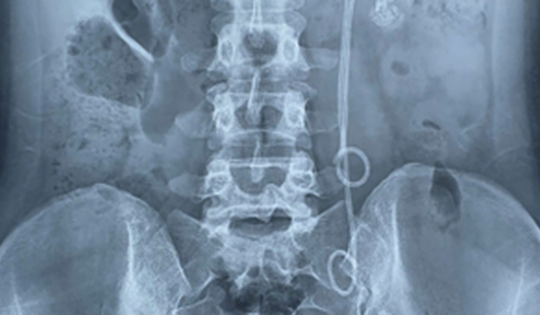

Người phụ nữ 33 tuổi đau tức thắt lưng, tiểu buốt, bác sĩ gắp ra thứ "đáng sợ" bên trong

Vừa qua, khoa Ngoại Tiết niệu – Bệnh viện 19-8 (Bộ Công an) đã tiếp nhận và điều trị thành công một ca bệnh hiếm gặp, khiến cả ê-kíp phẫu thuật phải xử trí hết sức thận trọng.